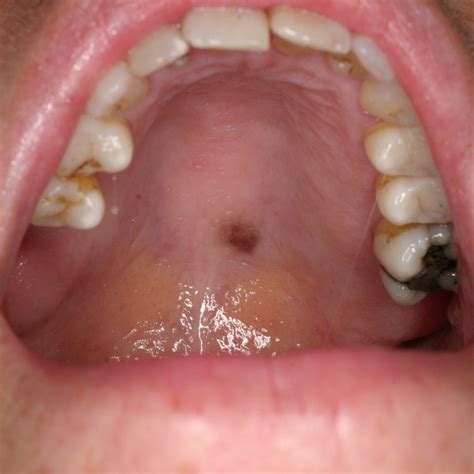

The roof of the mouth, also known as the palate, is divided into two parts: the hard palate and the soft palate. The hard palate is the bony front portion, while the soft palate is the muscular back portion. The hard palate is covered by a mucous membrane, which can sometimes become discolored, leading to a mouth roof yellow appearance.

Symptoms of a Yellow Mouth Roof

The primary symptom of a yellow mouth roof is the discoloration itself. However, other symptoms may accompany this condition, including:

• Sores or ulcers on the palate

Diagnosing a Yellow Mouth Roof

• Examine the mouth and palate for signs of discoloration and other abnormalities.

• Perform tests to rule out other potential causes, such as infections or oral cancer.